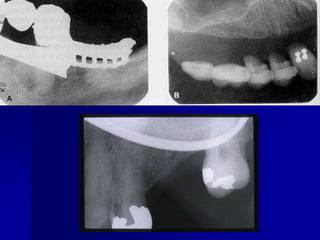

Technique & Projection errorsb. Film placmentartifactApices cut offOccur when the film is not positioned apically enough to record the entire tooth.

Technique & Projection errorsb. Film placmentartifactCrown not shown There is no enough film extending occlusally.

Technique & Projection errorsb. Film placmentartifactDropped film cornerThe film edge is not placed parallel to the occlusal surface of the teeth.

Technique & Projection errorsb. Film placmentartifactArea of interest not shownThis is the result of not placing the film to cover all the teeth in the area of interest and not centralizing the film over the area of interest.

Technique & Projection errorsc. Projection errorsPID alignment artifactIf the PID is misaligned and the x-ray is not centered over the film, a partial image is seen on the resultant radiograph, this partial image is called cone-cut.It appear as a clear area with curved outline.